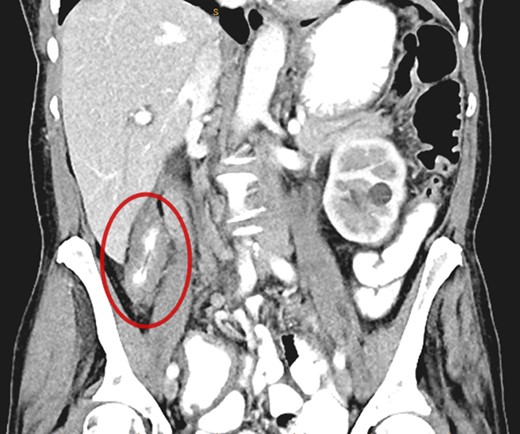

A 69-year-old otherwise well female with no prior history of malignancy underwent colonoscopy for investigation of upper abdominal pain, altered bowel habits—looser, more frequent stools—and subacute weight loss of 8 kg over a number of years. At colonoscopy, luminal narrowing, the impression of colonic thickening and very poor distension was encountered at the ascending colon (Fig. 1). The colonoscope was unable to traverse the narrowed segment. The remainder of the colon was unremarkable and there was no evidence of diverticulosis. Given the normal appearance of the mucosa at the area of presumed pathology, deep biopsies were taken using a bite-on-bite technique in order to ensure that submucosa was captured in the sample. Upper endoscopy was also performed and was normal.

A CT abdomen/pelvis performed on the same day demonstrated contiguous bowel wall thickening from terminal ileum extending to distal ascending colon. There was no evidence of disease elsewhere; notably, there was no evidence of peritoneal disease or ascites.